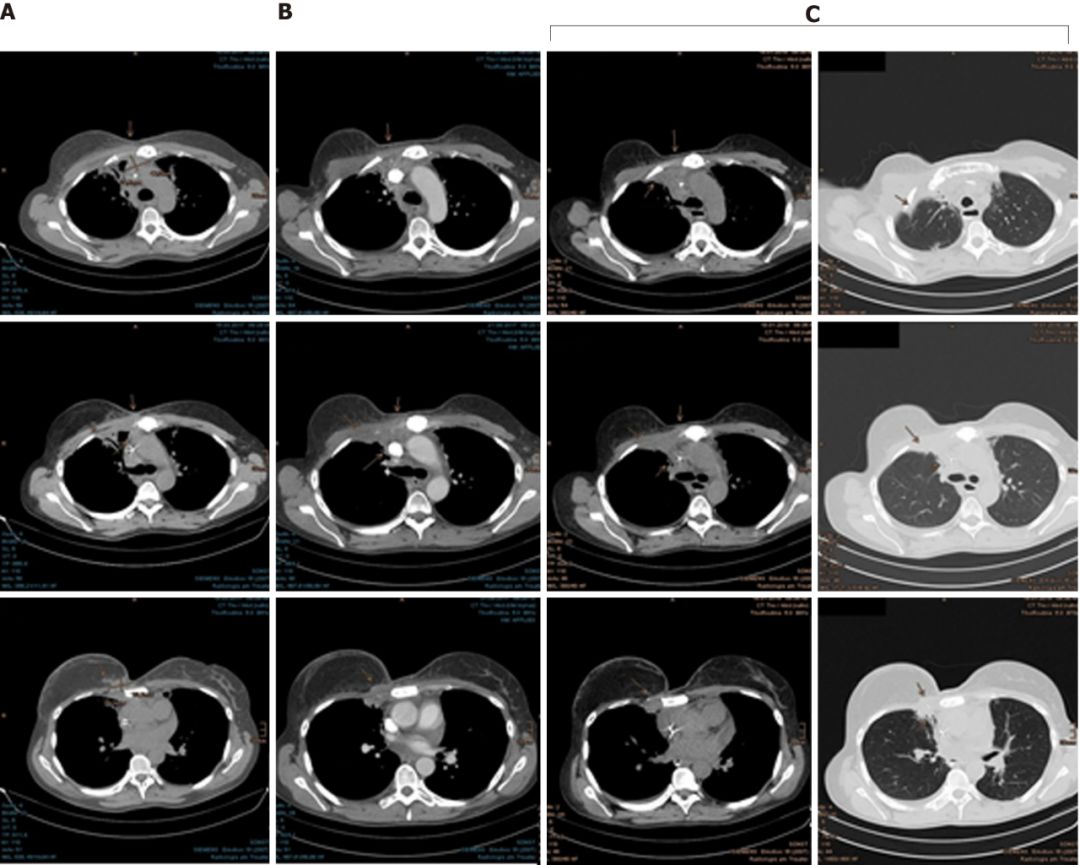

2015年7月,CT扫描发现肿瘤已经侵入肋软骨和腹侧胸膜,她的癌症全面复发了。

2016年11月至12月,Mary接受了右侧胸骨肿瘤以及邻近胸膜,右侧腋窝,胸骨旁和纵隔区域的淋巴结转移的质子放疗。

幸运的是,Mary对质子治疗的耐受性很好,仅出现了轻微的咳嗽和反流。由于对肺部有一定的辐射剂量,她吃了一些环丙沙星预防放射性肺炎的发生。随后的检查结果显示,癌细胞终于耐不住质子的强烈攻击,开始节节败退,病灶在一次次的缩小。

在最近一次CT扫描中,仍然没有发现肿瘤进展迹象。为了预防病情进展,Mary现在继续使用来曲唑和denosumab进行全身治疗。